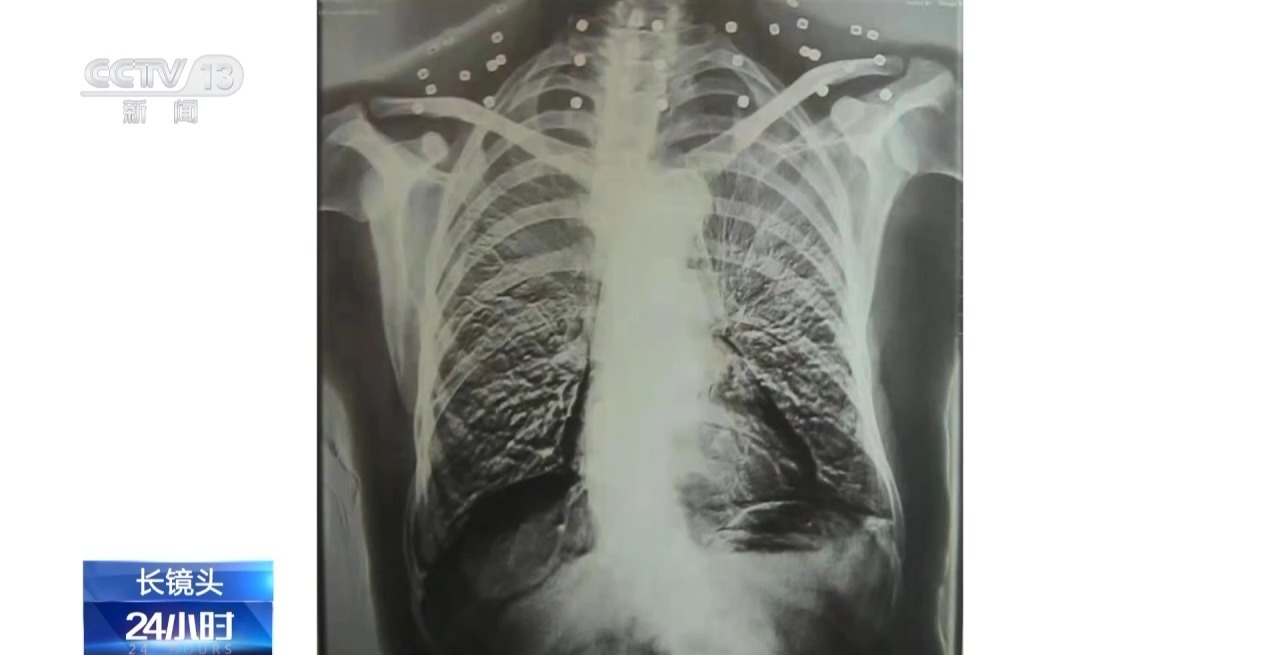

这张CT照片是82岁吴以先老人的CT照,当初拍片时,医生说,“老先生,您要把项链取下来再做CT。”

吴以先老人跟医生说,“可我从来没戴过项链,怎么会有项链呢?你看会不会是弹片?”自此,引出了一段老人不平凡的往事。

二十年前,吴以先老人做CT检查时发现,他的颈部有许多弹片,医生当时把弹片误认为是老人戴的项链,于是提醒他要把项链取下来再做检查。

吴以先:体检医生发现的,他一看,他说像一串项链一样的,他说你看这个病人脖子上的项链都没有取下来,好大一串项链。我说我从来没有戴过项链,这不是项链吧,我说是不是弹片,你们看看。

这是吴以先老人体内的33颗弹片,也是老人摘不下来的“项链”。